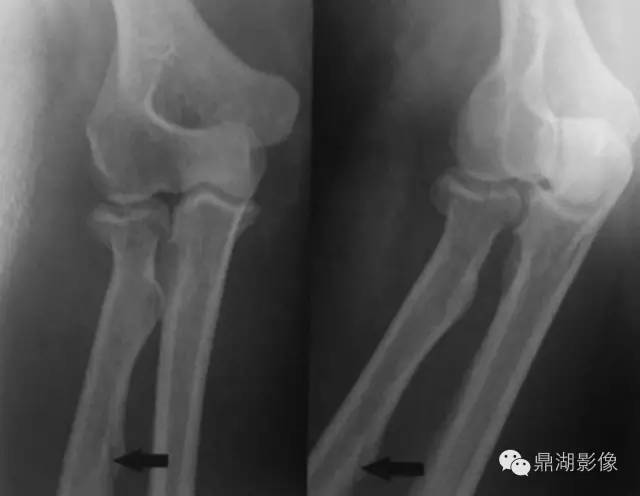

今天遇到一位外伤病人,右侧桡骨皮质区可见线样透亮影,与下图相似:

您会不会诊断骨折呢?我想不少人都会怀疑骨折可能。

但是,这其实桡骨的滋养管经典部位,认识这一解剖结构非常重要,以免将患者误诊为骨折。

所谓滋养孔,即是滋养血管穿过骨头时留下的空洞。一般要很大型的骨头才会有滋养血管,例如像上、下肢的几根主干骨那种级别的,比如肱骨,股骨,腓骨,胫骨。人体骨头上还有些孔其实关节腔的组成部分,全身206块骨头有很多都跟邻近的骨头合作构成关节,表面当然就会有凹陷、突起或者像孔一样的结构了。另外还有一些孔是血管和神经经过造成的,例如颅底的那些小孔。这种孔并非是固定的,如果人体有变异,那么它们也会被改造,位置和形状就变化了。